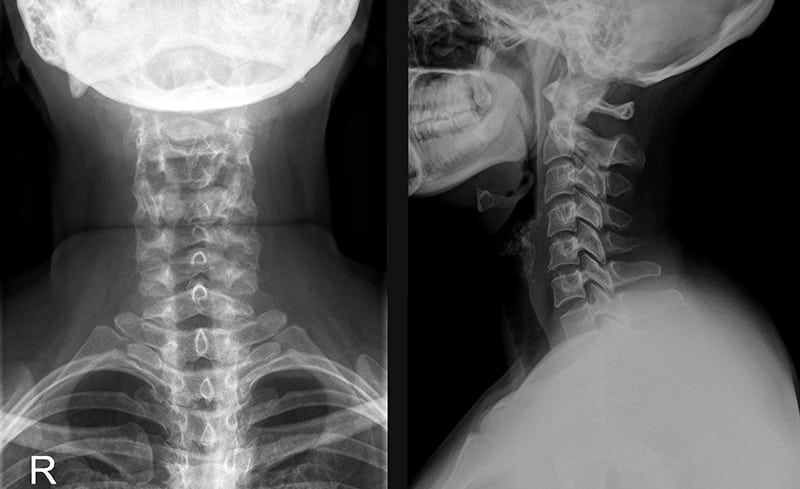

Диагноз выставляется на основании внешнего осмотра пациента, его жалоб, наличия в анамнезе системных заболеваний, предшествующих травм. На шейно-плечевой остеохондроз указывают синюшный оттенок кожи, отечность, изменения контуров пораженных позвонков. Наиболее информативным инструментальным диагностическим методом является рентгенография.

Рентгеновский снимок больного остеохондрозом.

По полученным трехмерным изображениям можно с высокой точностью установить локализацию деструктивно-дегенеративного процесса, стадию его течения, степень повреждения костных, хрящевых тканей, связочно-сухожильного аппарата. Дифференциальная диагностика проводится для исключения артрита, остеомиелита, остеопороза, артроза.